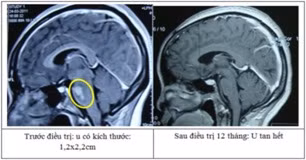

Tính đến nay có gần 4000 u não và bệnh lý sọ não được điều trị thành công bằng kỹ thuật sử dụng dao gamma quay và nhiều bệnh nhân không phải ra nước ngoài điều trị.

![]() |

| Kỹ thuật sử dụng dao gamma quay là kỹ thuật xạ phẫu tiên tiến trên thế giới, đưa Việt Nam trở thành một trong những nước đầu tiên trong trị u não |